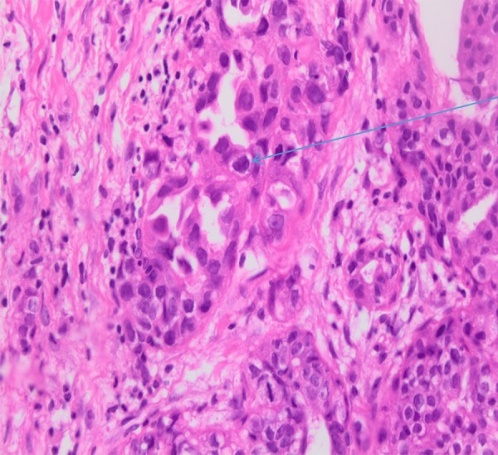

Immunohistochemical staining for Cytokeratin 7, demonstrating the diffusely infiltrating carcinoma in the submucosa, muscular wall, mesenteric adipose tissue, and serosa (Courtesy Dr. V. Penopoulos)